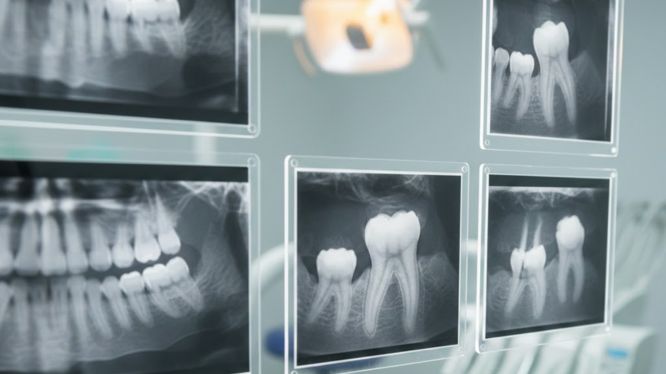

🦷 Radiografías intraorales: cuando se necesita ver el detalle

Por otro lado, las radiografías intraorales se toman dentro de la boca y permiten observar con gran precisión un diente o una zona específica.

🔹 Radiografías periapicales

Estas radiografías muestran:

• El diente completo

• La raíz

• El hueso que lo rodea

• La zona cercana al nervio

📌 Se recomiendan cuando:

• Hay dolor localizado

• Sospecha de infección

• Antes o después de una endodoncia

• Golpes o traumatismos dentales

🔹 Radiografías periapicales digitales

Son una versión más moderna y ecológica ♻️

✨ Ventajas:

• Eliminan el proceso de revelado químico

• Menor impacto ambiental

• Imagen más nítida

• Mínima distorsión

📌 Ideales para una revisión integral de los dientes y estructuras cercanas.